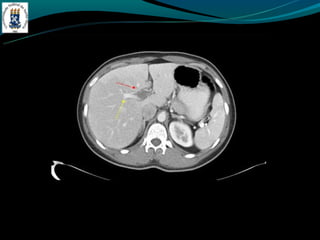

BUDD-CHIARI

-Hipercoagulabilidade

-Compressão – tumor

-Membrana da VCI

-Dor abdominal, hepatomegalia e ascite.

- TC: hepatomegalia heterogênea, não visualização das veias

hepática, ascite, realce hepático central, lobo caudado preservado

ou aumentado.

BUDD-CHIARI -Hipercoagulabilidade -Compressão – tumor -Membranada VCI -Dor abdominal, hepatomegalia e ascite. - TC: hepatomegalia heterogênea, não visualização das veias hepática, ascite, realce hepático central, lobo caudado preservado ou aumentado.